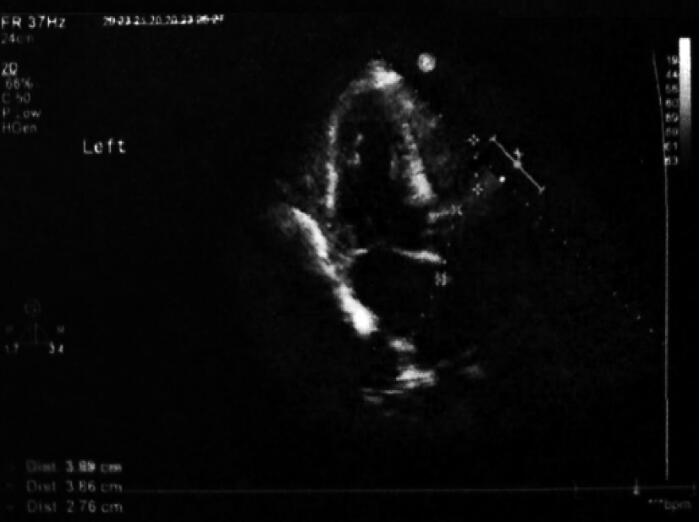

入院辅助检查:本次入院连续3次血培养均为屎肠球菌,对万古霉素、庆大霉素、链霉素均敏感。心脏超声:主动脉瓣置换术后,生物瓣轻中度狭窄并轻度关闭不全,主动脉瓣生物瓣呈团块状,EF 54%(图5)。腹部B超示:脾大(图6)。

图5 入院94天超声心动图结果

主动脉瓣为人工瓣,瓣架固定,瓣叶增厚,呈团块状,瓣周未见明确异常回声附着,余各瓣膜形态结构未见异常主动脉瓣人工瓣向前血流速度最大约为3.3m/s,平均压差约25mmHg,且可见少量反流信号。超声提示:主动脉瓣置换术后,生物瓣轻度狭窄并轻度关闭不全,主动脉瓣生物瓣呈团块状